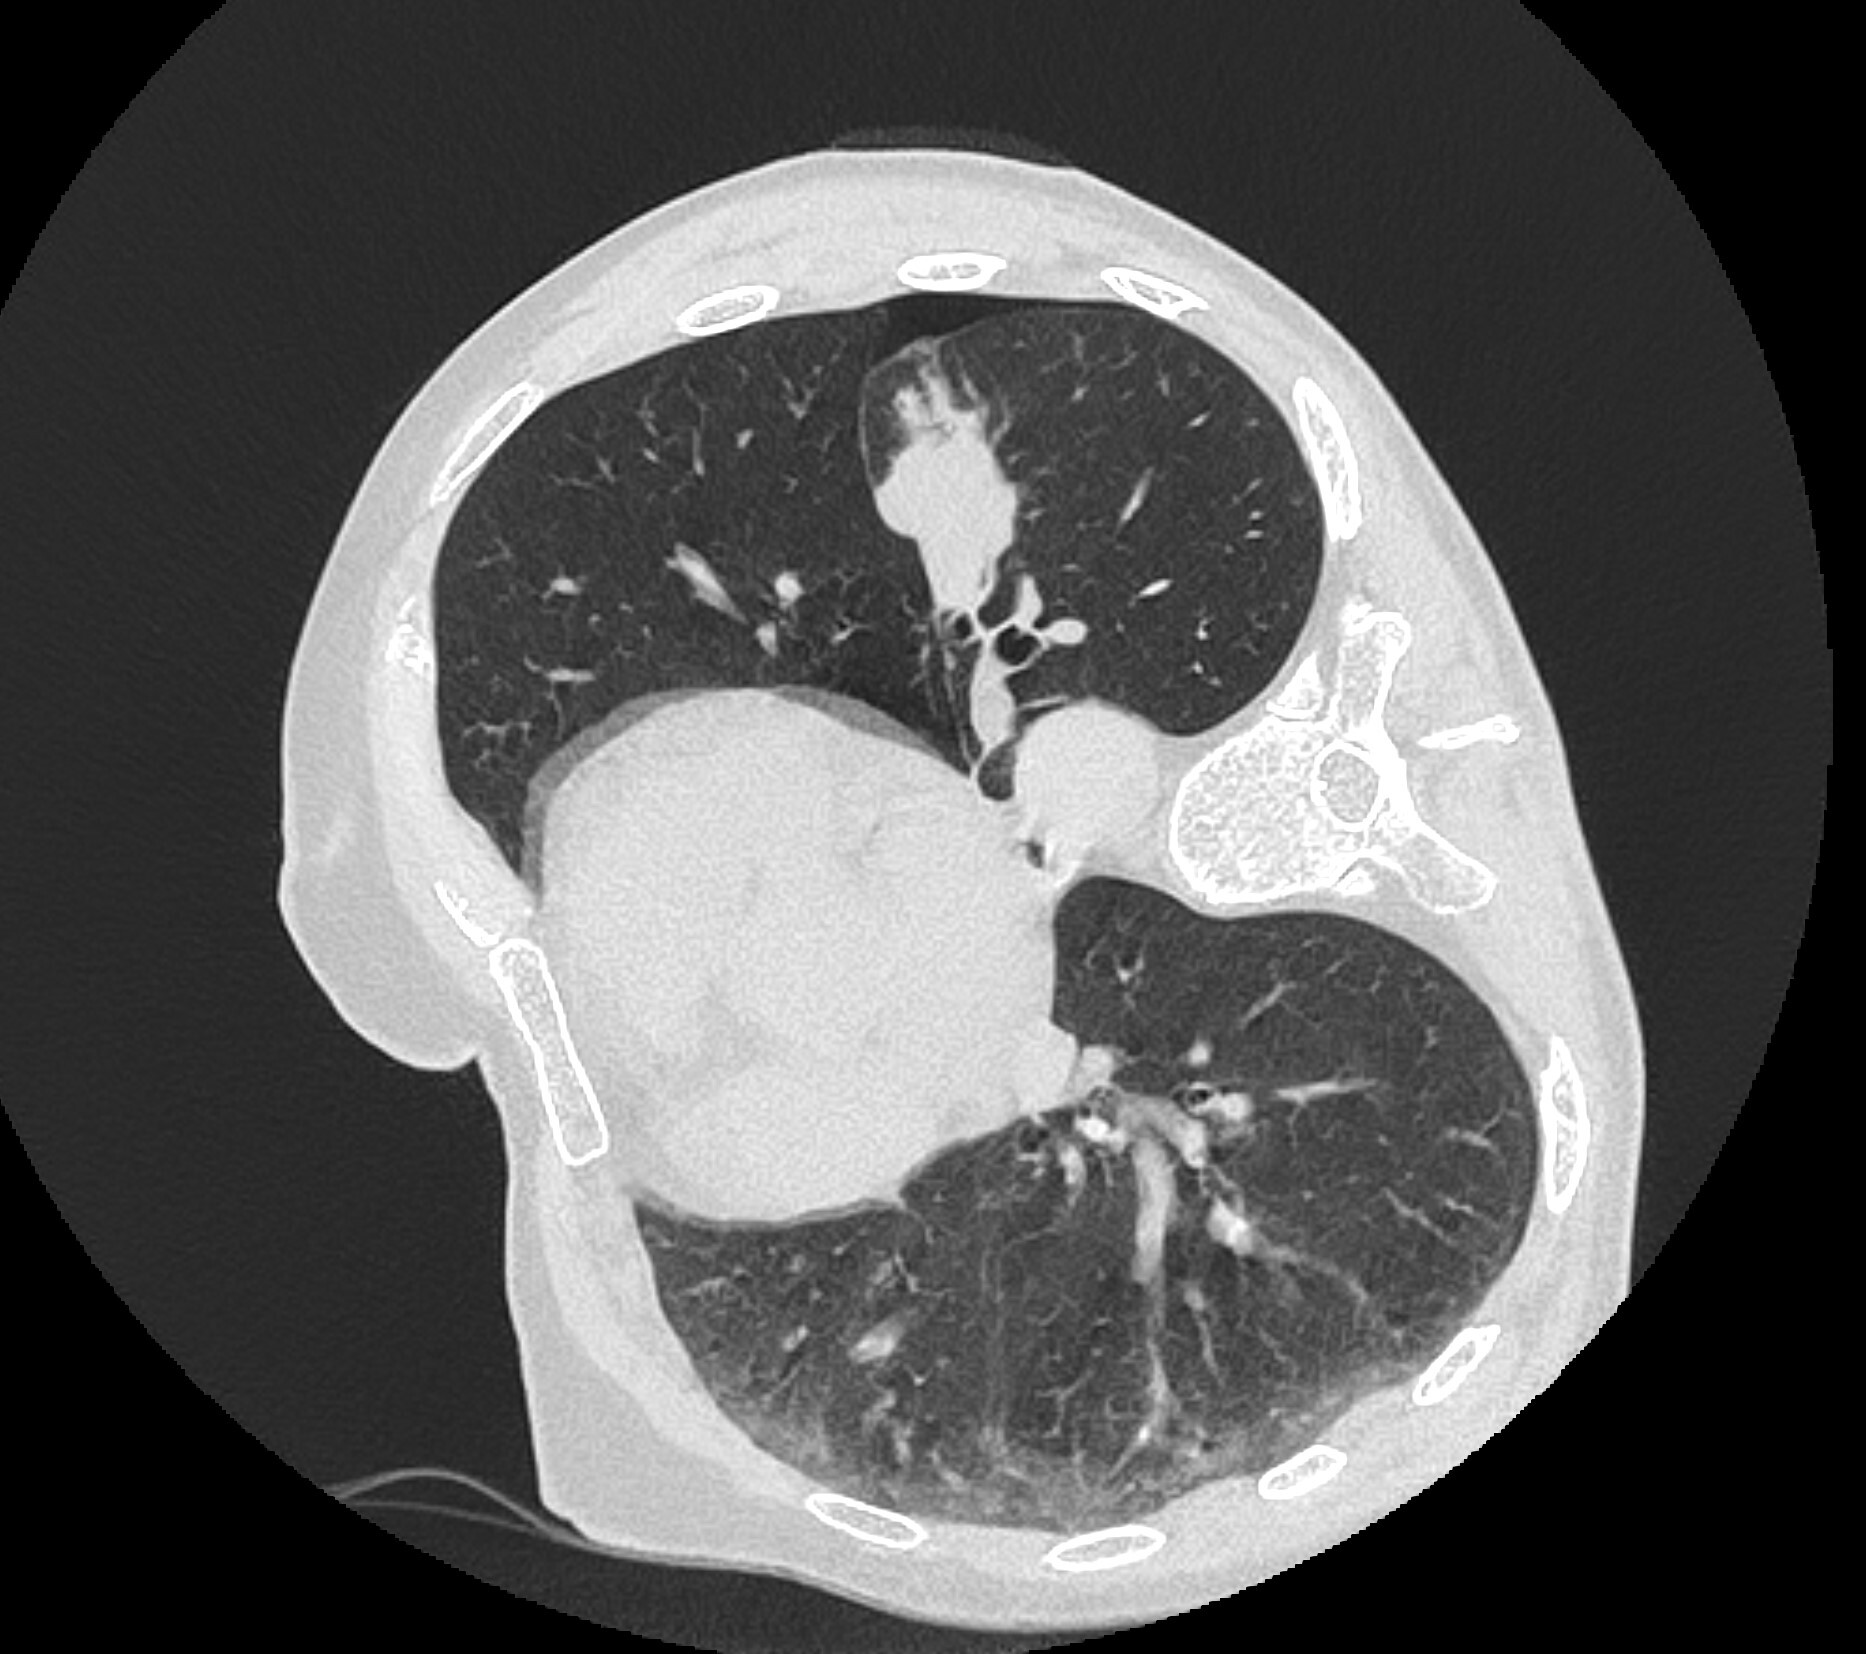

Но вот контрольный скан после интервенции показал небольшой пневмоторакс (черная область в лёгком):

Беда конечно, но без паники! Он небольшой, так что ещё не всё так плохо. Уложили больного на левый бок, чтобы место пункции было придавлено весом пациента, попросили лежать так 1 час и отправили его в дневной стационар (пункция амбулаторная).